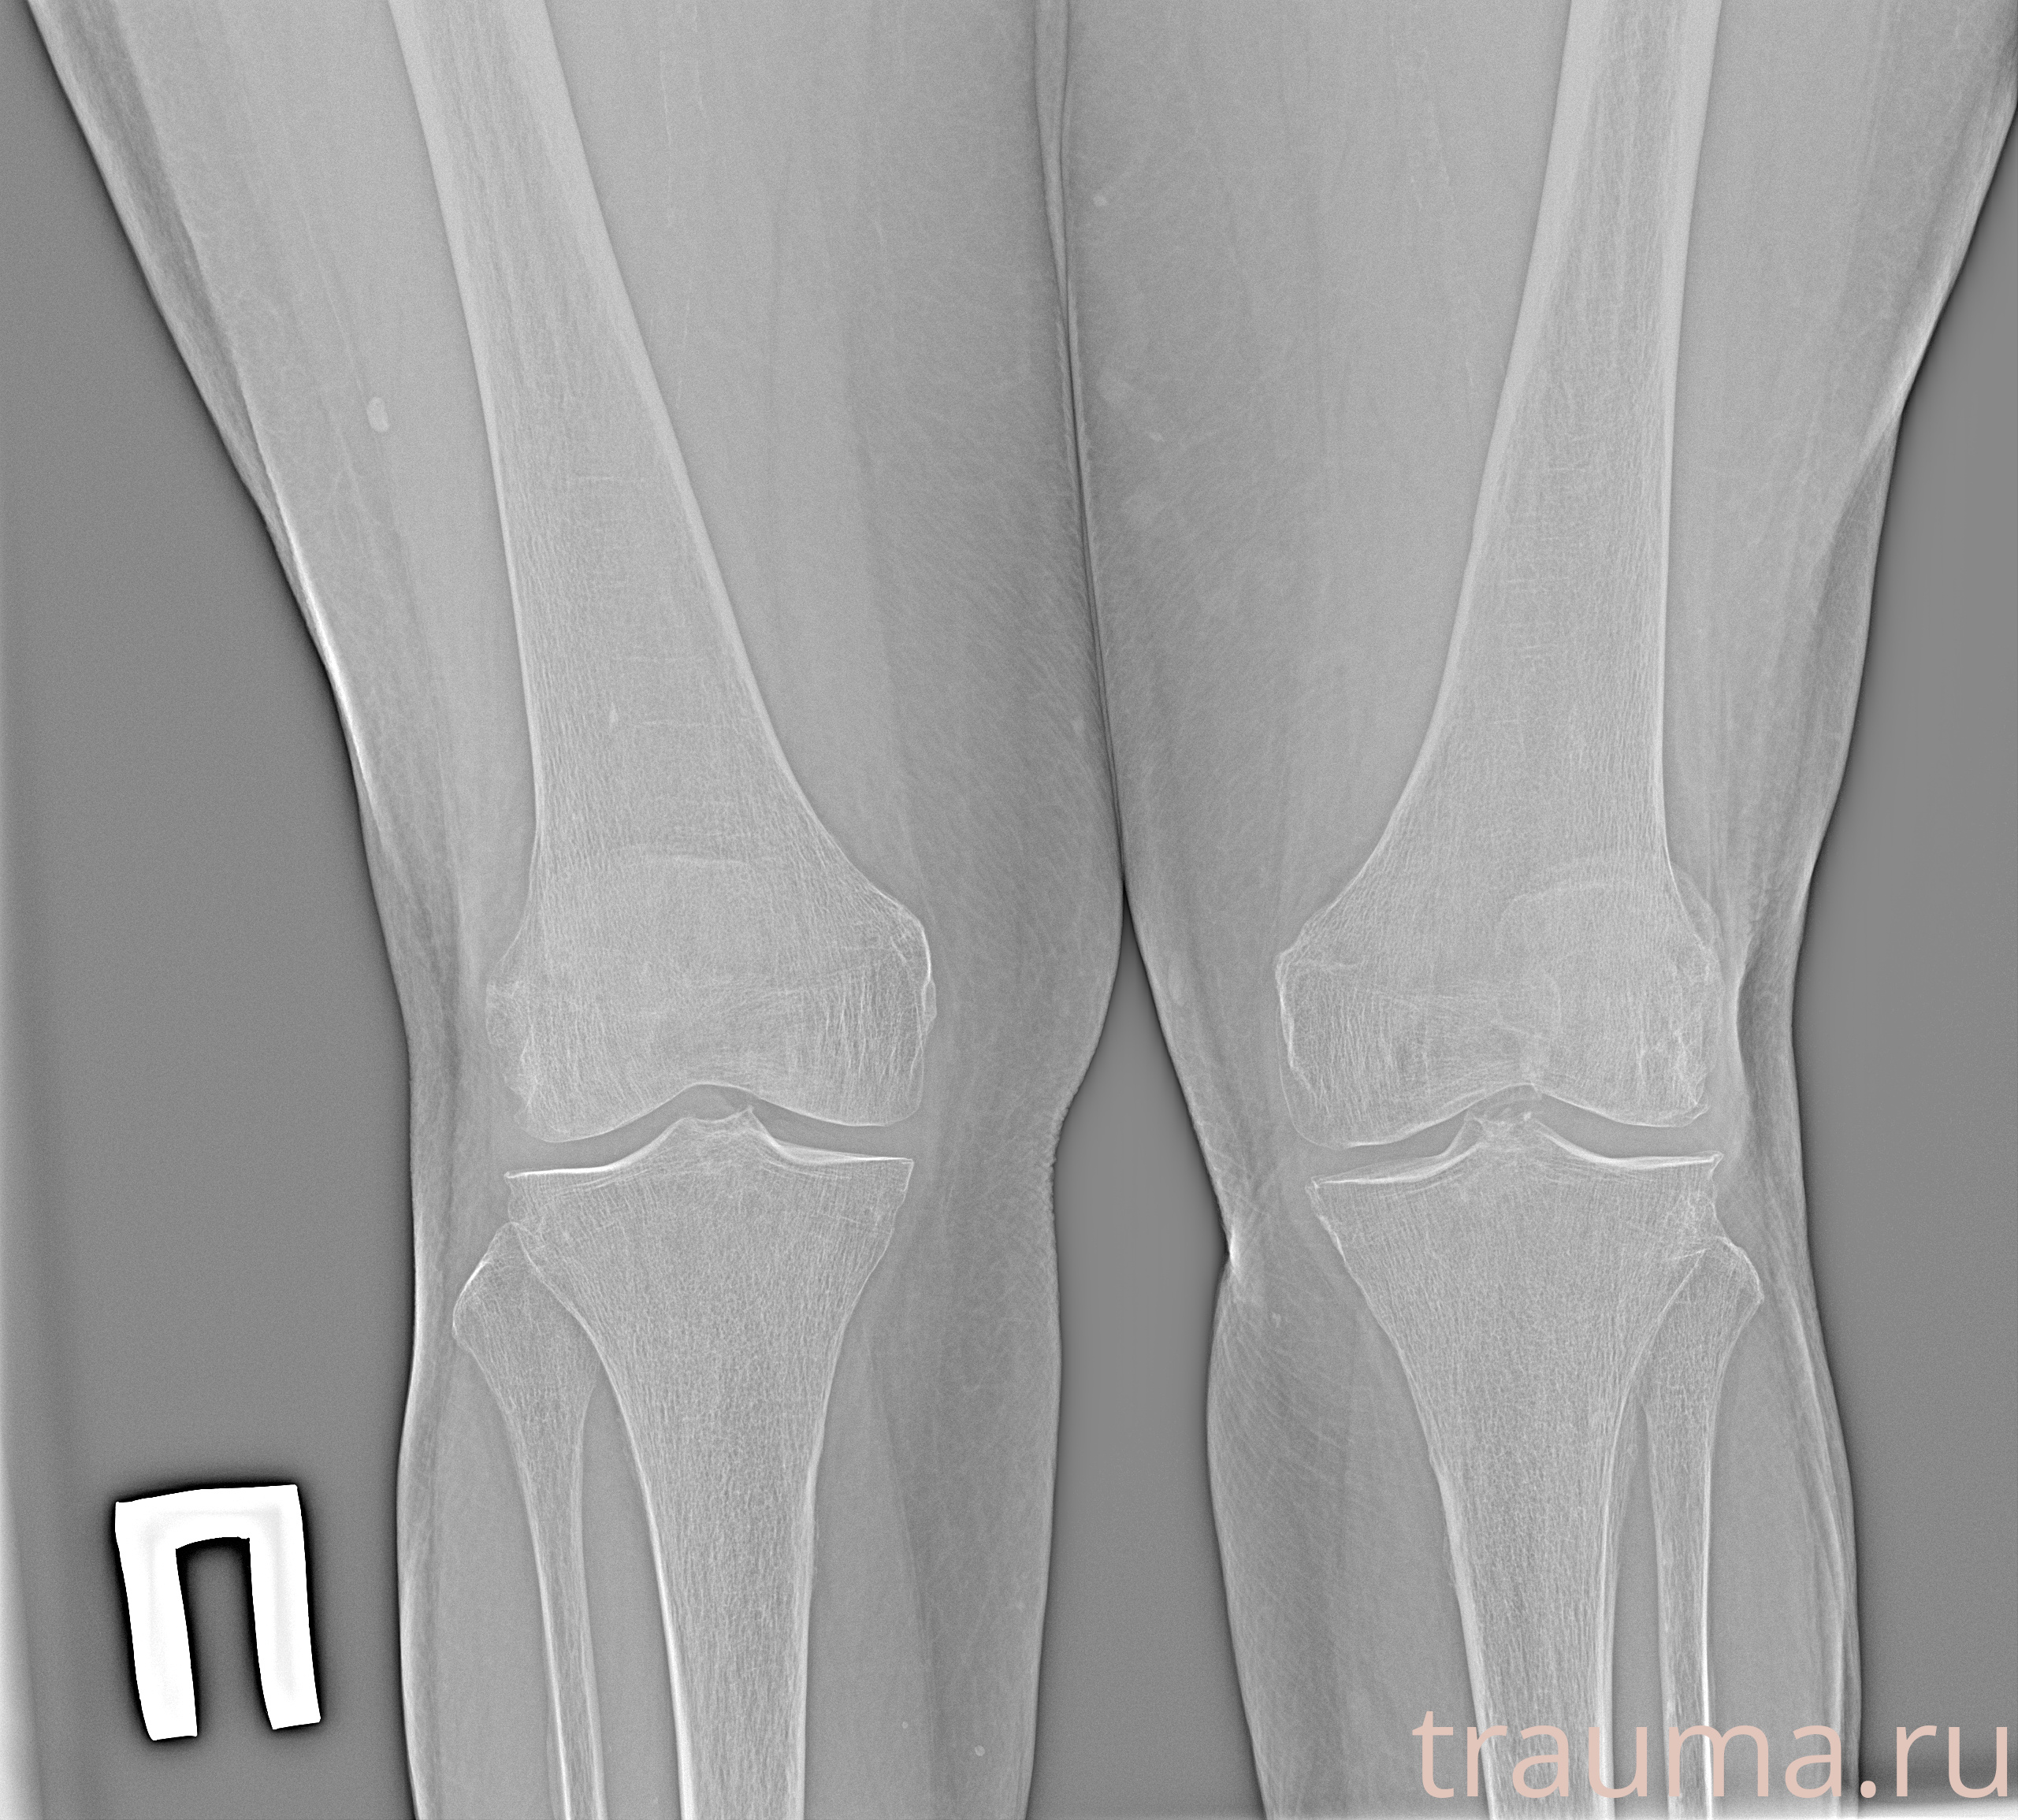

Рентген на дому: по вашему адресу приезжает врач-рентгенолог, травматолог-ортопед с мобильным рентгеновским аппаратом, проводит диагностику травмы или заболевания, делает необходимые рентгенограммы, дает рекомендации по дальнейшему лечению. Получить качественные снимки в домашних условиях возможно благодаря уникальной методике, разработанной МосРентген Центром для института  Склифосовского